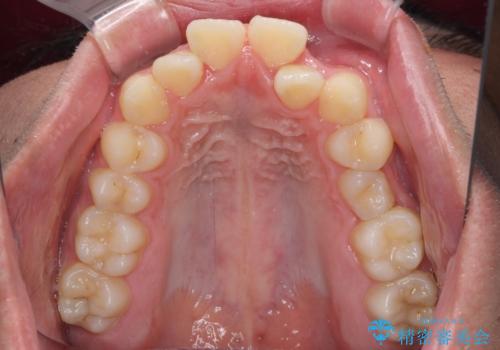

- 前歯のデコボコと口元の突出感を気にして来院された患者様です。

上下前歯がくちばしのように突出していたため、上下左右の第一小臼歯4本を抜歯し、ワイヤー装置にて矯正治療を行うこととしました。

左上は第二小臼歯が90度捻れており、状態が良くない歯であったため、左のみ第二小臼歯を抜歯することとしました。

上顎骨に対して下顎骨がやや前方位に位置しているため、下顎前歯をあまり内側に移動させることができず、口元の突出感改善は期待以上にはならないと予測しておりましたが、満足いくの引っ込み具合となりました。